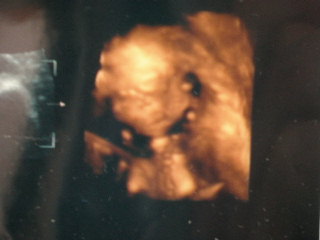

A babakép lemaradt!